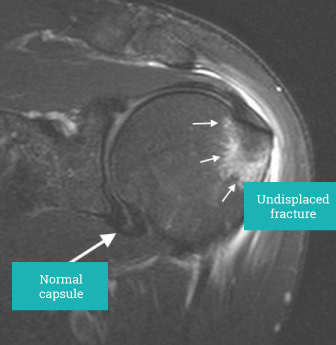

The proximal humerus may fracture into multiple fragments or individual single pieces of bone associated with the attachment of the rotator cuff. Each of these fractures require careful assessment and if displaced surgical management as they are the attachment of the rotator cuff.